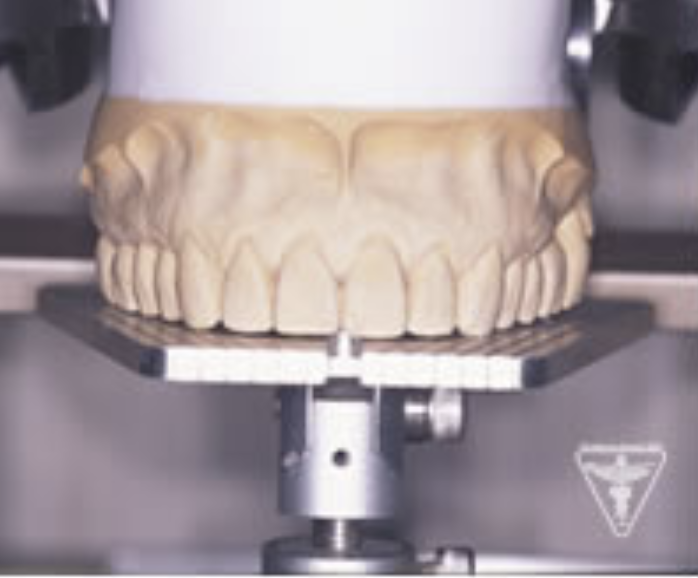

治療前

下の奥歯が左右なくなっており、かみ合わせが深くなっています。

顎のずれは認めませんが、歯肉が厚く中に炎症を取りこみやすいタイプの歯肉です。

左の顎の骨が大きく溶けてなくなっております。